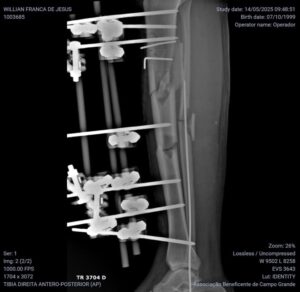

Atualmente, ele convive com fixadores externos na perna e precisa, com urgência, passar por dois procedimentos fundamentais:

• a retirada desses fixadores, e

• a colocação de uma haste intramedular de titânio, que permitirá a estabilização correta do osso e a chance real de voltar a andar com segurança.